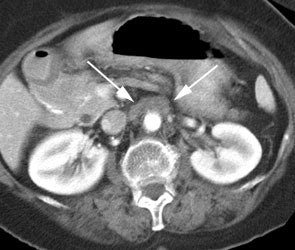

Rising CEA level: The patient below had a history of treated colorectal carcinoma and a rising CEA level. The FDG PET exam demonstrated foci of abnormal tracer uptake in the liver and pelvis (black arrows). Subtle abnormalities could be identified on the CT exam and subsequent surgical exploration confirmed the presence of metastatic disease (white arrows). |

Recurrent colorectal cancer: The patient shown below had a history of colon cancer and a rising CEA level. FDG PET exam revealed a site of tracer uptake in the mesentery (black arrows) which corresponded to an enlarged lymph node seen retrospectively on CT scan (white arrow). |

|